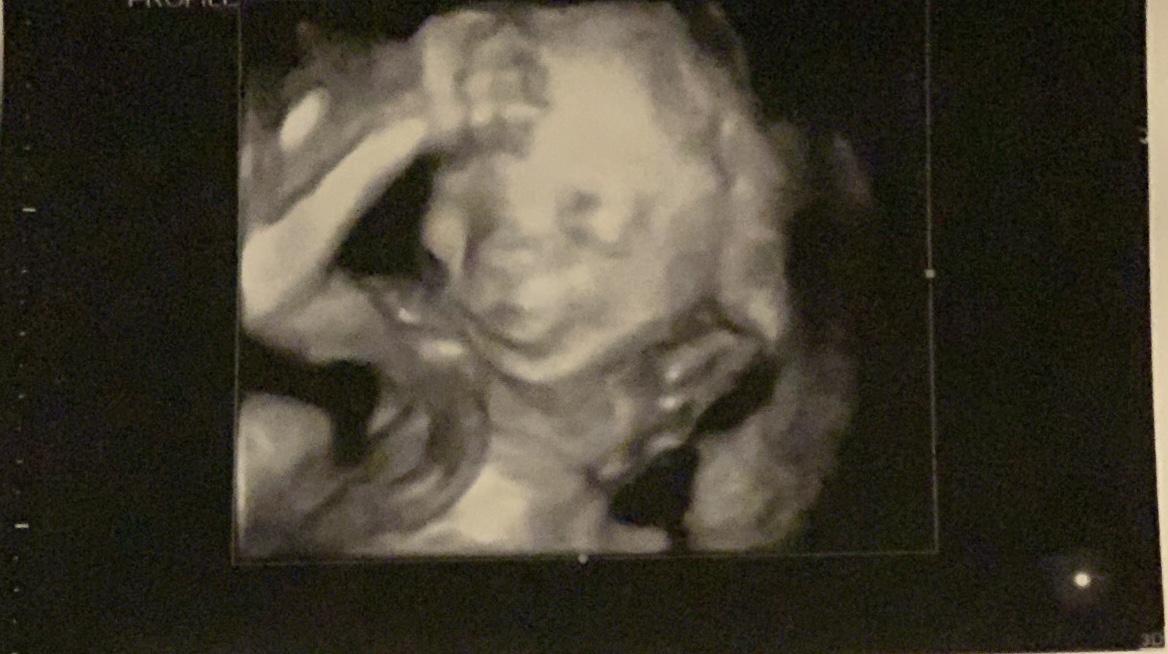

Jade's Baby Registry